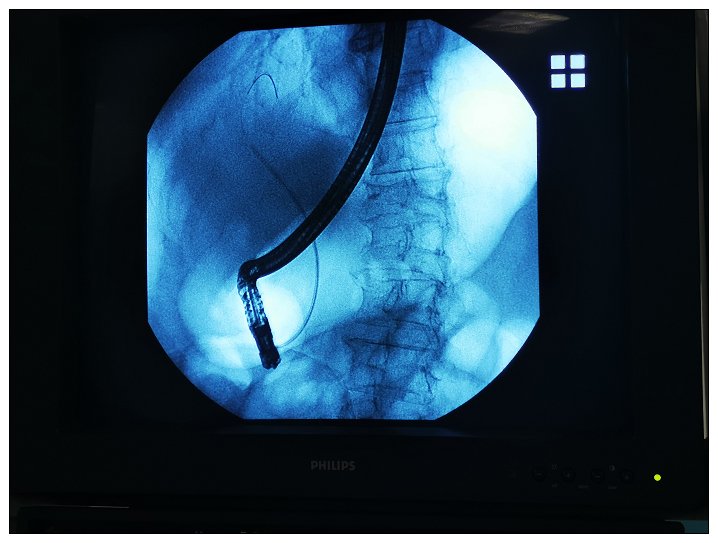

2020年元旦,一78岁男性患者因腹痛收住消化内科,经积极检查,CT显示急性胰腺炎、胆总管结石、肝硬化。当天晚上患者出现发热,体温高达40.4度,伴黄疸,且凝血时间延长,血小板降低。请肝胆外科会诊,由于患者年龄大,病情危重,不适宜外科手术,建议急诊放置鼻胆引流管引流。当晚22点,急诊做了ERCP术(经内镜逆行性胰管造影)。术后患者腹痛明显缓解,早晨体温也正常了,达到立竿见影的效果。2020第一仗,打得漂亮。